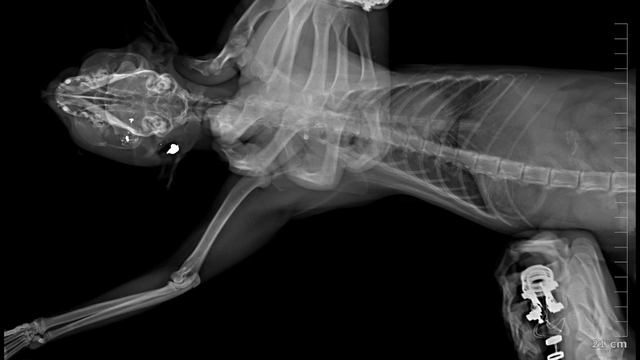

İpsala ilçesine bağlı Köprü Mahallesi'nde 2018 yılından bu yana devam eden kedi ölümlerine ilişkin hayvansever Hüseyin Bülbül, olayın peşine düştü. Bülbül, son 7 yılda beslediği kedilerin bazılarının ortadan kaybolması, bazılarının ölü bulunmasının ardından sokağın belirli noktalarına güvenlik kamerası yerleştirdi. Hüseyin Bülbül ayrıca ölü bulunan kedileri özel bir kliniğe götürdü. Klinik raporunda, 'ateşli silah yaralanması ile uyumlu patolojiler' tespit edildiği, hayvanların tüfek saçması sonucu öldüğüne ilişkin bulgulara yer verildi. Bülbül, güvenlik kamerası görüntülerinden komşusu K.G.'den şüphelendi. Görüntülerde; K.G.'nin bahçesine giren bazı kedilerin aniden kaçtığını fark etti.

İpsala Cumhuriyet Başsavcılığı'nın olaya ilişkin hazırladığı iddianamede K.G., hakkında, 'Bir ev hayvanını veya evcil hayvanı kasten öldürme' suçundan 6 aydan 3 yıla kadar hapis cezası istendi. İddianamede, "Herhangi bir silah ateşleme görüntüsü tespit edilmese de şüphelinin ikamet ettiği evin bahçe kapısı önünde bir kedinin can çekiştiği ve bir kedinin de kaçtığının tespit edildiği, dosya kapsamında tanık olarak beyanı alınan S.Ç.'nin şüphelinin bahçe kapısı önünde bir kediyi yatar vaziyette gördüğünü, başını sevmek istediğinde kedinin ölü olduğunu fark ettiğini, kediyi eline aldığında başından kan aktığını görmesi üzerine yol üzerinde kalmaması amacıyla kediyi çöp tenekesinin içerisine bıraktığını, ölen ve yaralanan 2 kedi hakkında düzenlenen 25/08/2025 tarihli veteriner hekim ön muayene raporu ile çekilen radyografilerde ateşli silah yaralanması (kuş saçması) ile uyumlu patolojiler gözlemlendiği şeklinde rapor tanzim edildi. Tüm dosya kapsamı incelenmekle şüpheli savunması, bilgi sahibi beyanları, İpsala İlçe Tarım Müdürlüğü'nün yazılı başvurusu, müşteki beyanı, kamera görüntüleri ve kriminal raporları birlikte değerlendirildiğinde, şüphelinin olay tarihinde müşteki Hüseyin Bülbül tarafından da beslenmekte olan sokak kedilerine ateş etmek suretiyle, bir kedinin ölümüne neden olarak üzerine atılı suçu işlediğine dair ve bir kedinin yaralanmasına neden olarak tariflenen suçu işlediğine dair hakkında kamu davası açmak üzere yeterli şüphe oluşturacak kadar delilin mevcut olduğu anlaşılmakla" denildi.